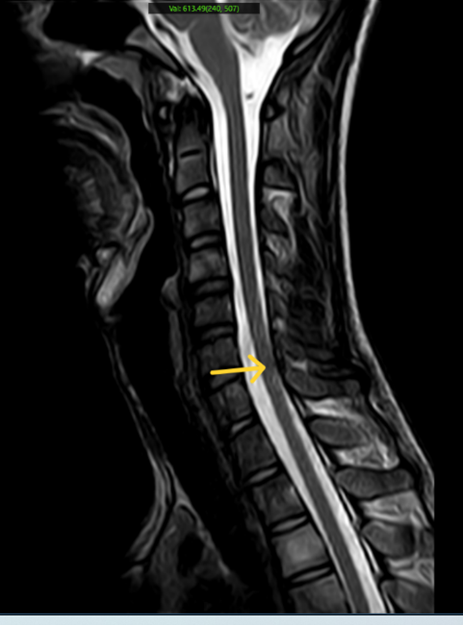

- Chụp MRI cột sống cổ: Hình ảnh phù tủy xương thân đốt sống C4, C6, C7, D1, D2, D3, gai ngang D1 bên phải và gai sau D2.

Hình 6: Hình ảnh MRI cột sống cổ có phù tủy xương thân đốt sống (mũi tên vàng)